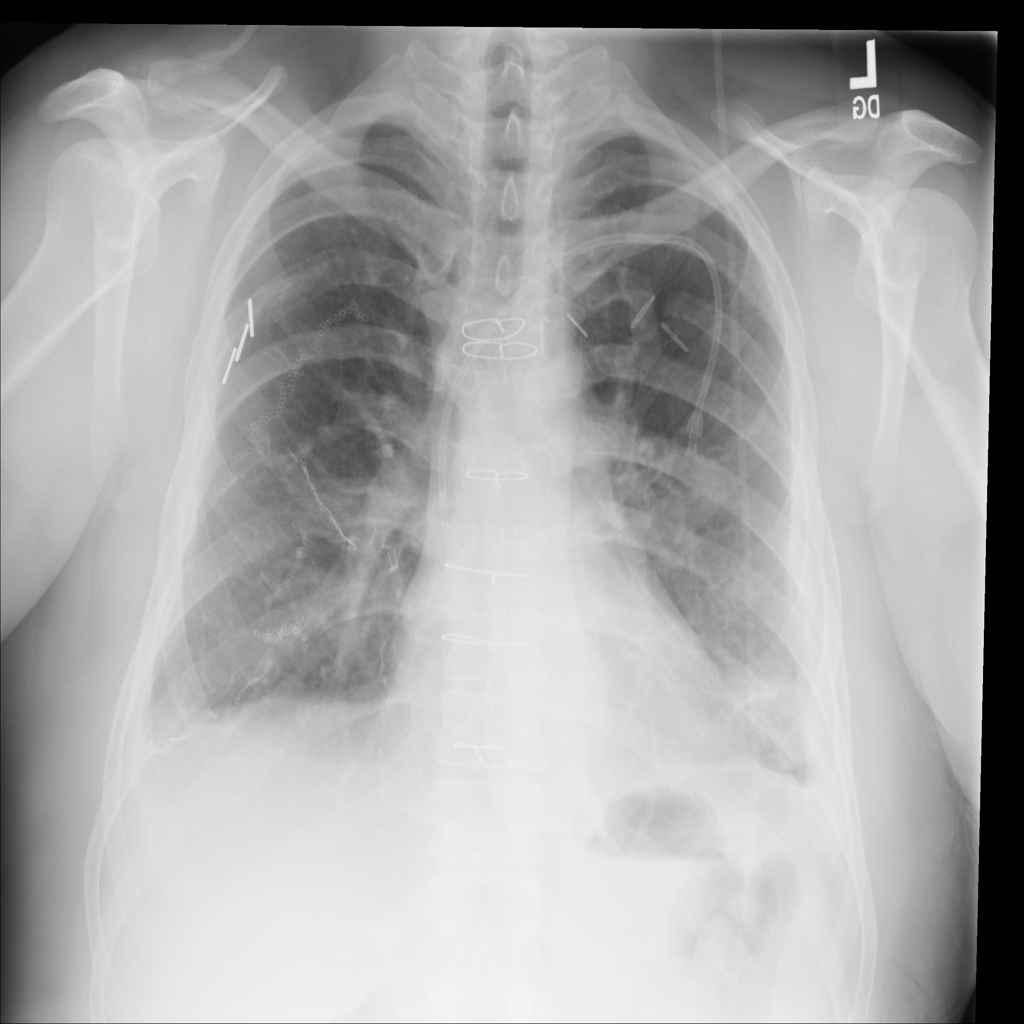

Showing up to 90 reference images for Pneumothorax.

PAT-4639 · IMG-020Pneumothorax

PAT-4639 · IMG-020

PA